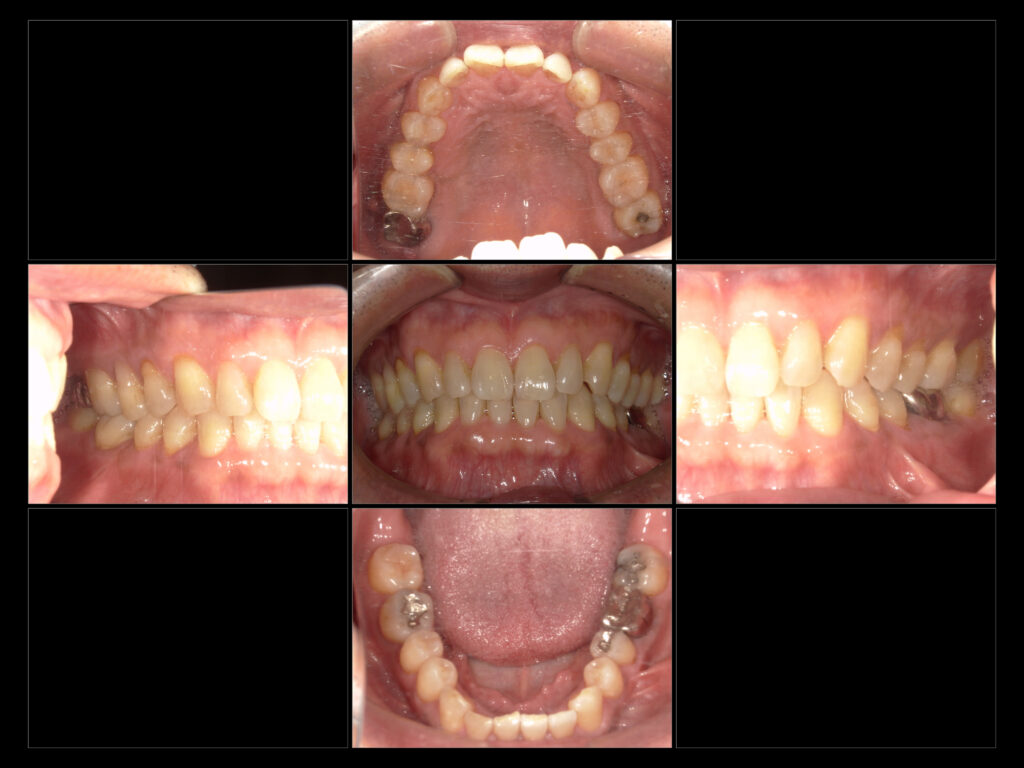

↑初診時口腔内写真